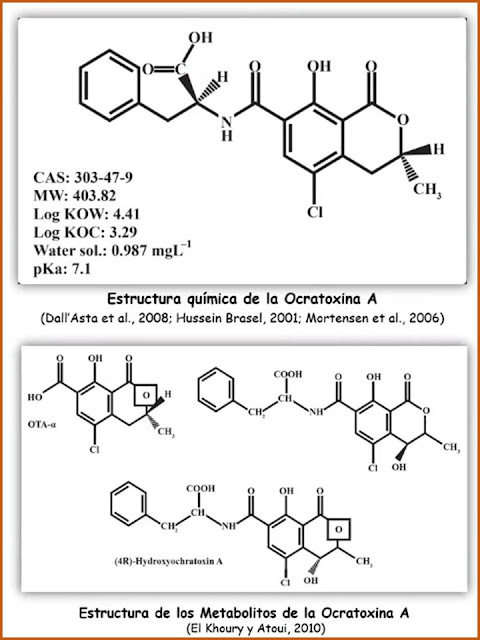

La ocratoxina A (OTA) es una toxina producida por hongos de los géneros Aspergillus y Penicillium, con propiedades nefrotóxicas, inmunotóxicas, teratogénicas y carcinogénicas; que ataca granos almacenados, entre ellos el cacao.

Las ocratoxinas son consideradas metabolitos secundarios en los géneros Aspergillus y Penicillium, encontrándose en cacao y sus derivados, Cuando son procesados o almacenados en condiciones de alta humedad y temperatura.